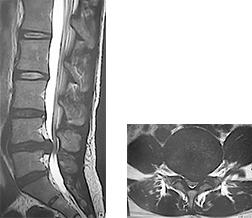

腰椎椎間板ヘルニア

どんな病気?

せぼね(脊椎)は7個の頚椎、12個の胸椎、5個の腰椎と仙椎から構成されます。腰椎は主に5つの骨と、間にあるクッションのような椎間板、また神経組織が通っている脊柱管から成り立っています。椎間板ヘルニアとは、椎間板の中央にある髄核の一部が周りにある線維輪の亀裂から出て、後方の脊髄や神経根を圧迫してしまう病気です。原因は加齢、重量物の挙上など外的な負荷、スポーツなどの外傷、また近年では遺伝的な関与も指摘されています。腰椎椎間板ヘルニアは20~40歳代に発症することが多く、男女比は約2:1と言われています。

検査方法

椎間板の傷み具合や膨隆の程度、不安定性の有無、またせぼね全体のバランスなどを見るためにX線検査やCT検査、MRI検査などを行います。その他、入院して行う脊髄造影検査や、神経の枝に直接麻酔薬を注入する選択的神経根ブロック、あるいは椎間板造影や椎間板ブロックを行うこともあります。成人期では血管性の下肢の痛みがないか評価するために両手足の血圧を測ったり、骨粗鬆症の有無を評価するために骨密度検査を行うこともあります。